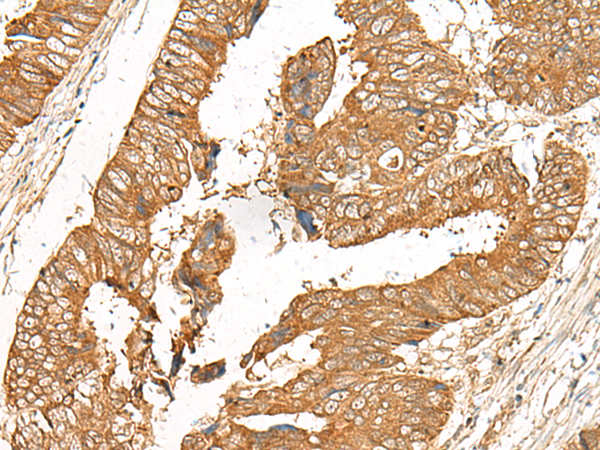

(The image is immunohistochemistry of paraffin-embedded Human colorectal cancer tissue using 47586(GOLGA6A Antibody) at dilution 1/50.(Original magnification: 200))

IHC (Immunohistochemistry)

(The image is immunohistochemistry of paraffin-embedded Human cervical cancer tissue using 47586(GOLGA6A Antibody) at dilution 1/50.(Original magnification: 200))